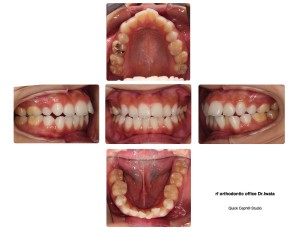

今の歯並びや噛み合わせがどうなっているのか、

顎の骨の形状や虫歯の有無を精密に調べるためにレントゲン撮影と写真撮影を行います。

写真は口の中だけでなく顔写真も撮影します。

正面の顔写真は顔や顎の歪みを、そして笑った写真は歯の見え方を見るために撮影するそうです。

撮影後は口の中のチェックをして、撮影した写真を見ながらカウンセリングを受けました。

お見苦しいですが、私の歯は上の歯が出っ歯で、下の歯はガタガタしています。